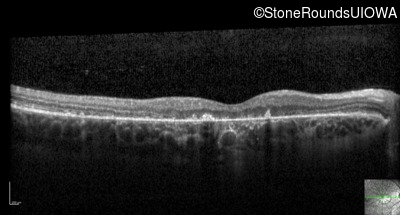

Optical Coherence Tomography - Left - 20/150 sc

Exemplar / OCT Stack

OCT Stack